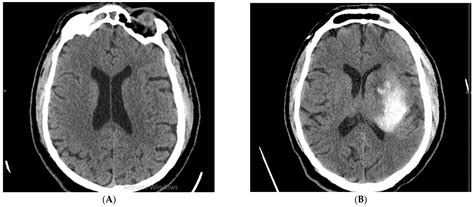

Computed Tomography (CT) scans are essential in the diagnosis of ischemic stroke. An Ischemic Stroke CT scan can quickly and accurately detect the presence of a stroke, differentiate it from other conditions, and guide treatment decisions. The scan uses X-rays to create detailed images of the brain, which can reveal:

• Hemorrhage: Whether the stroke is ischemic or hemorrhagic, which is crucial for determining the appropriate treatment.

• Non-contrast CT (NCCT): This is the most basic type of CT scan and is often the first test performed. It provides a clear view of the brain structures and can detect early signs of ischemia, such as the “dense artery sign,” which indicates a blood clot.

Interpreting the results of an Ischemic Stroke CT scan requires expertise and experience. Radiologists and neurologists work together to analyze the images and make a diagnosis. Key findings that may be observed include:

• Early ischemic changes: These can appear as areas of low density (hypodensity) in the brain tissue, indicating reduced blood flow.

• Hyperdense artery sign: This is a bright appearance of an artery on a non-contrast CT scan, suggesting the presence of a blood clot.

• Mass effect: Swelling or compression of brain tissue due to the stroke, which can be seen as a shift in the midline structures of the brain.

• Case 1: Early Detection: A 65-year-old patient presented with sudden weakness on the left side of the body and difficulty speaking. An Ischemic Stroke CT scan revealed a blood clot in the right middle cerebral artery. Thrombolytic therapy was administered within the critical time window, leading to a full recovery.

• Case 2: Complex Diagnosis: A 50-year-old patient with a history of atrial fibrillation experienced a sudden onset of vision problems and dizziness. A CT scan showed early ischemic changes in the brainstem. Further imaging with CTA and CTP confirmed the presence of a blood clot and guided the decision for mechanical thrombectomy.